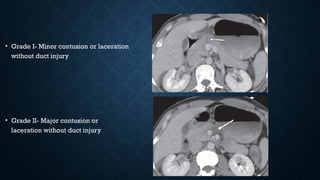

• Grade I- Minor contusion or laceration

without duct injury

• Grade II- Major contusion or

laceration without duct injury